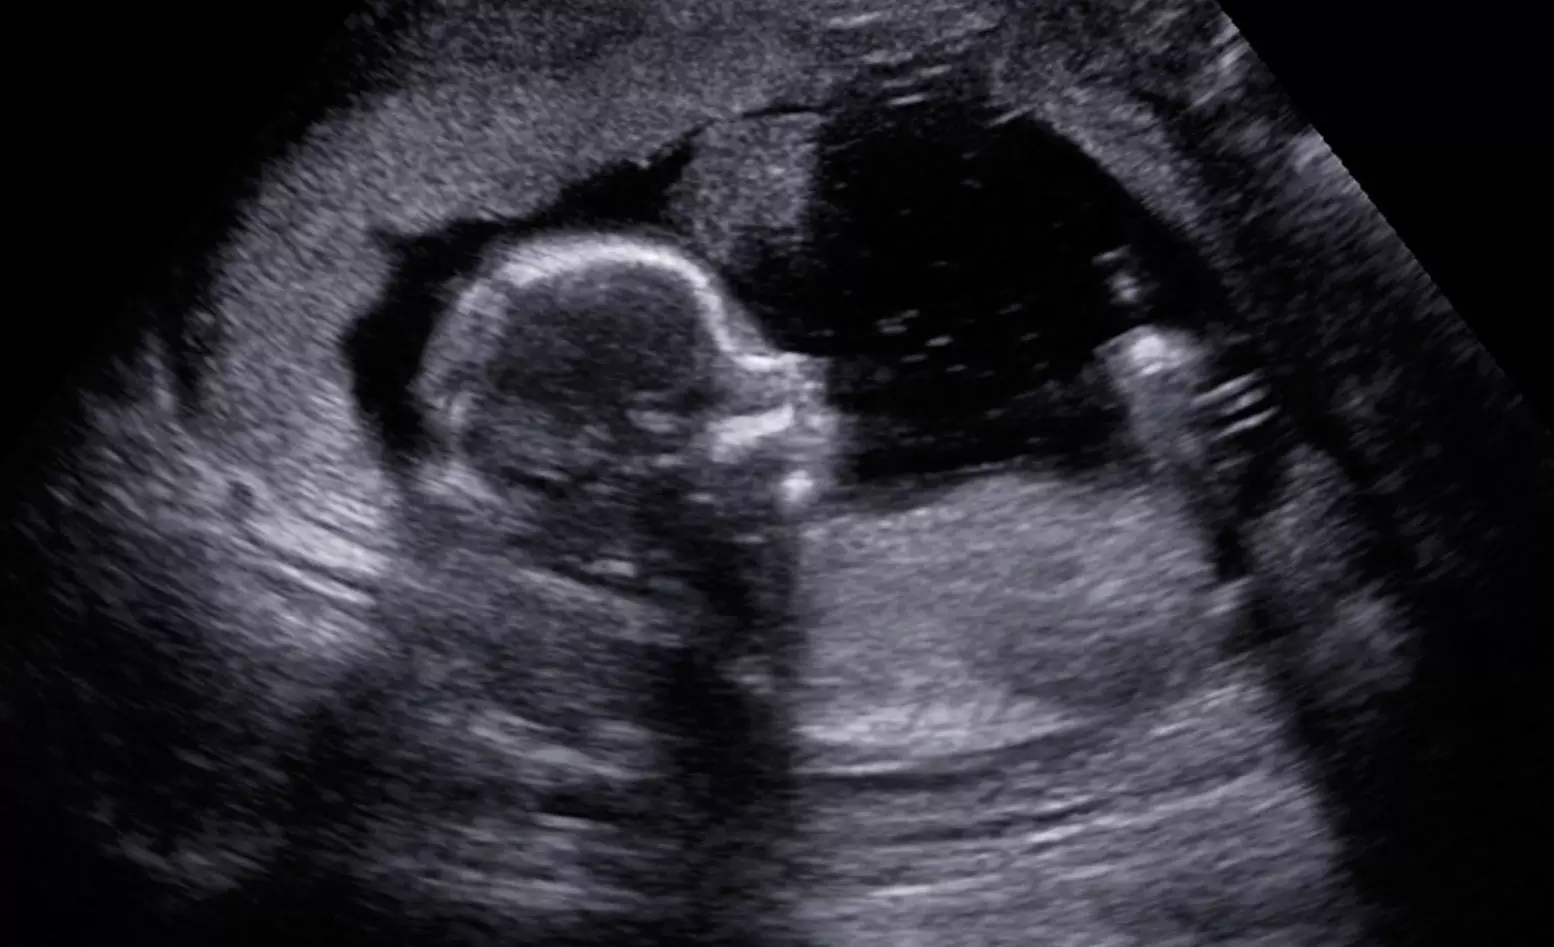

But Daysha, a mom whose chemical abortion was reversed with the APR protocol, and who gave birth to her son in just the last two months, was among those who testified before Indiana lawmakers about the success of APR as the law was being considered.

Daysha had her son in March.

“He weighed 6 lbs., 13 oz.,” Daysha’s representative told Indiana legislators for her, “and he’s healthy.”

“I’m so glad I had him,” she said. “I made a mistake, and I am so glad I could reverse the pills.”